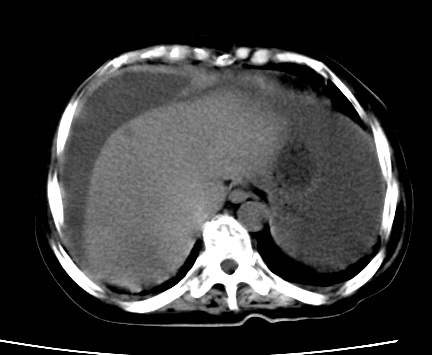

标题: CT23975:女61岁,腹部不适,明显消瘦

既往5年前卵巢癌行子宫及附件切除,右乳癌术后一年,考虑腹膜转移?

大量腹水,考虑腹膜转移。肝脏低密度灶。1囊肿,2转移。

1)结合病史,考虑腹膜及网膜转移瘤。2)肝脏多发性低密度灶,不排除转移瘤。3)大量腹水。

考虑卵巢癌行子宫术后复发,并肝、腹腔 、大网膜转移可能性大。

大量腹水。